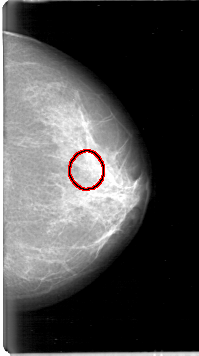

D_4054_1.LEFT_MLO

LEFT_MLO LINES 5386 PIXELS_PER_LINE 3001 BITS_PER_PIXEL 12 RESOLUTION 43.5 OVERLAY

FILE: D_4054_1.LEFT_MLO.OVERLAY

TOTAL_ABNORMALITIES 1

ABNORMALITY 1

LESION_TYPE CALCIFICATION TYPE MILK_OF_CALCIUM DISTRIBUTION CLUSTERED

ASSESSMENT 0

SUBTLETY 3

PATHOLOGY BENIGN

TOTAL_OUTLINES 1

BOUNDARY